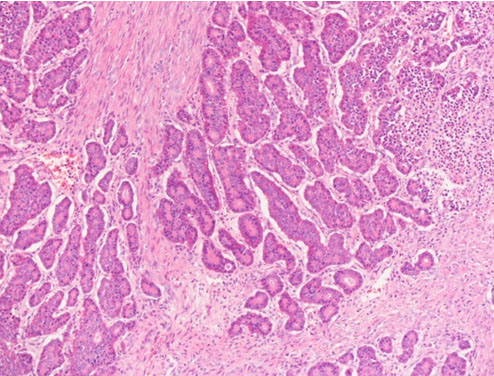

Sections of left ovary showed involvement by tumor tissue. The latter was composed of nests, acini, and trabeculae of tumor cells separated by dense fibrous tissue. The tumor cells featured low columnar to cuboidal cells with regular round nuclei, stippled chromatin, and eosinophilic cytoplasm with abundant red-brown granules. Mitosis was seen at less than 1/10 high power fields. Lymphoplasmacytic infiltrates were noted focally. Ovarian tissue was noted in the peripheral of tumor, and the ovarian capsule was intact (Figure 2 and Figure 3).

Figure 2: Case 1 carcinoid tumor under low power field, × 100. There are nests of tumor cells with fine chromatin. The tumor cells are in clusters.

Figure 3: Case 1 carcinoid tumor under high power field, × 400. It is composed of nests, acini, and trabeculae of tumor cells separated by dense fibrous tissue. The tumor cells feature low columnar to cuboidal cells with regular round nuclei, stippled chromatin, and eosinophilic cytoplasm with abundant red-brown granules.